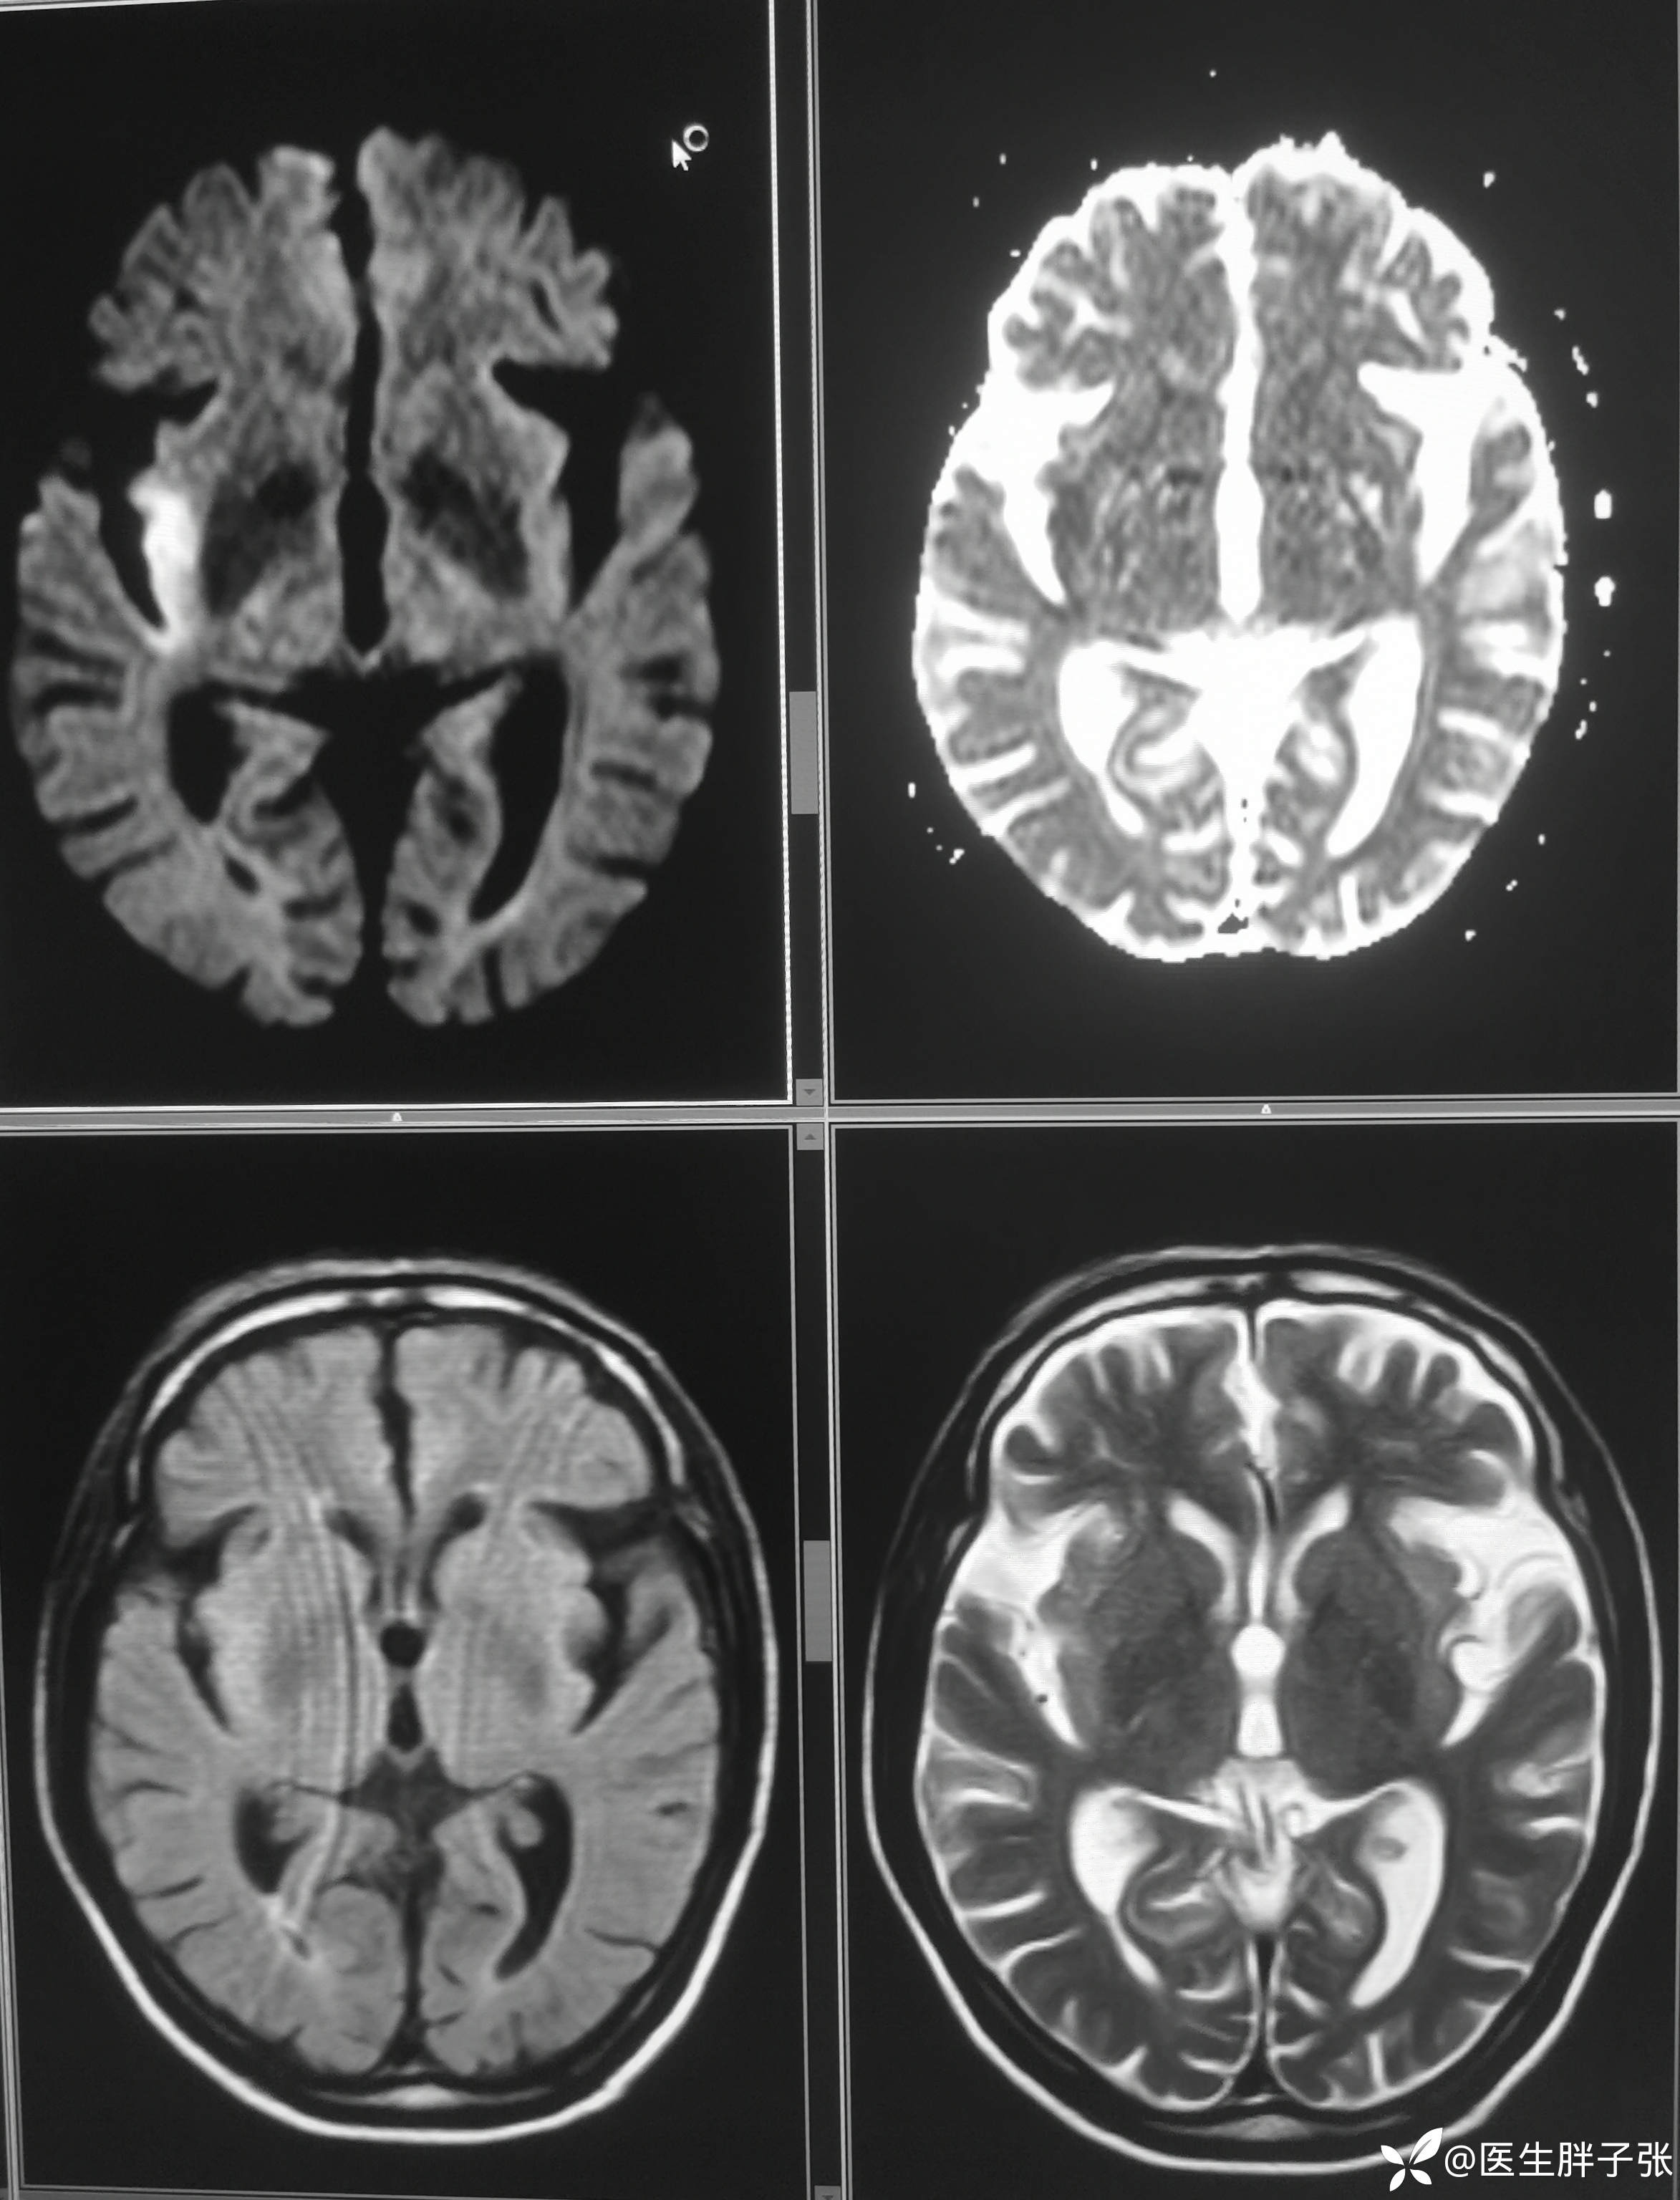

颅脑MR:右侧颞叶新近梗死灶;老年性脑改变;右侧大脑中动脉部分M2段及以远未见显示,建议头颈部CTA检查。

患者为醒后卒中患者,幸运的是恰好晨起交班的时候来院,恰好能查核磁,核磁提示存在DWI-FLAIR错配

溶栓过程顺利,无并发症。患者发病前有腹泻,MRA提示右侧大脑中M2闭塞可能